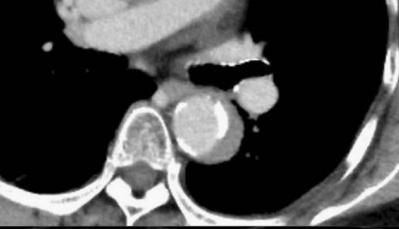

下面这个CT平扫,

这里有大问题!

很可惜,这个不是问题,很多CT平扫都有这种线样阴影!

下图是:隐隐约约不肯定有血管内线样阴影!